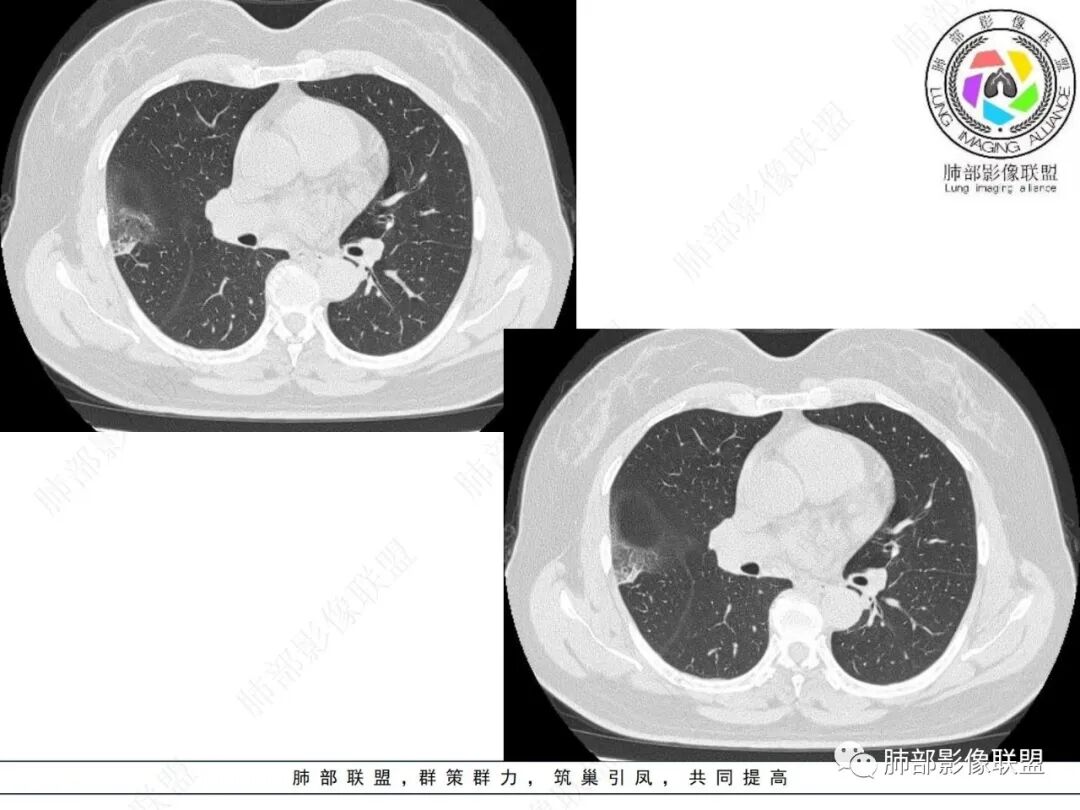

右肺上叶胸膜下混合磨玻璃团片影。

周围磨玻璃部分间杂条索状高密度区,密度欠均匀(可疑重力分布趋势),其磨玻璃影边界大多较清楚或可分辨,部分“L型”边缘,提示小叶间隔阻挡可能。血管穿行自如,可疑远端支气管进入。

实性部分较密实,不规则,隐约见棘突或刺状突起,未见钙化、空洞或液化区,实性边缘可见斑状略低密度间隙(借用王兆宇老师课件,称其呈“松软”的形态)。动脉期实性部分较明显不均匀强化,如果有完整增强图,还可以观察内部血管情况。

右肺上叶胸膜下混合磨玻璃结节,磨玻璃部分与实性部分密度都不均匀,病灶有重力分布效应,小叶间隔阻挡,收缩力羸弱。中老年女性,如此大范围病灶,缺乏临床表现,会让人警惕非感染性病变,尤其是恶性病灶可能!

病灶磨玻璃部分边界较清楚,有重力分布趋势,可能会想到黏液腺癌,或者分泌粘液的腺癌的可能性。不支持地方也有,如实性部分密度偏高,病灶强化程度偏高等。